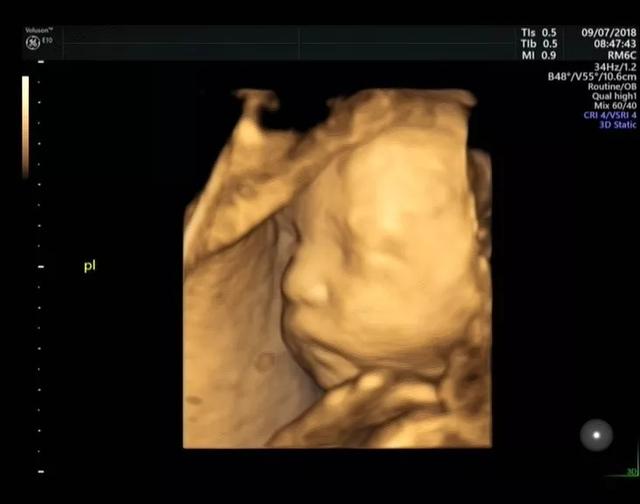

1、传统的B超只能简单的观察到胎儿的四肢是否健全和模糊的胎儿动态,但是四维彩超检查,能清晰的观察到宝宝在妈妈肚子里的即时动态和各种神态,还能立体清晰的看到妊娠中晚期胎儿的全貌,更能检测到宝宝的四肢和内脏发育情况。

2、四维彩超能多方位,多角度地诊断胎儿各器官的发育情况,可以精确筛查先天性畸形,例如骨骼发育异常、唇裂等症状,有利于胎儿早期诊断治疗。

3、四维彩超能对胎儿的体表进行检查,能够准确、清晰检测出胎儿发育是否异常,及早检查胎儿的大脑、脊柱、骨骼、面部是否有发育不良的情况,以便尽早的进行治疗。

做四维彩超的最佳时间是因个人而异的,做四维彩超的需求不同得到的结果也会不同,孕期的22-28周是照四维彩超的最佳时间。因为胎儿24周左右正是大脑突飞猛进的发育时期,这个时期的胎儿结构已经形成,胎儿的大小以及羊水适中,在宫内的活动空间较大,胎儿骨骼回声影响比较小,图像也比较清晰。

选择在四维彩超的最佳时间里做检查,除了能够给孩子留下珍贵的影像记录以外,更重要的作用是排畸。各个孕期都可以进行四维超声检查,但最佳时间是怀孕22-28周,此时胎儿各主要脏器已发育,羊水量适量、胎儿已进入腹腔,便于胎儿畸形的筛查。